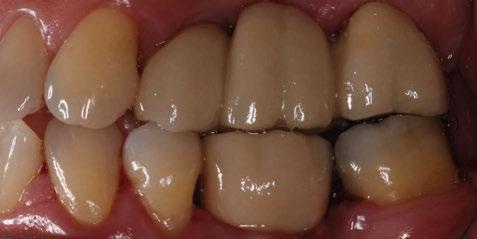

A partir del estudio radiológico y de las imágenes fotográficas podemos observar edentulismo de 17, 15, 14, 12,

Figura 1a. Foto intraoral frontal inicial.

Figura 1b. Foto intraoral lateral izquierda inicial.

Figura 1c. Foto intraoral lateral derecha inicial.

25, 26, 28, 37, 38, 47 y 48. Presentaba corona desajustada en 13 con extensión en 12, implantes en 35-36, 45-46, con coronas ferulizadas en 35-36, 45-46, y dientes anteriores superiores con enfermedad periodontal Grado IV.

El paciente presentaba biotipo periodontal grueso, con márgenes asimétricos, con recesiones gingivales a nivel de 11 y 13 y pérdida de tejidos blandos interproximales.

3. Exploración de tejidos duros

En la exploración radiográfica (OPG, CBCT) observamos la existencia de pérdida ósea interproximal, lesión apical a nivel de la raíz mesial del 27 y el cordal del primer cuadrante incluido y neumatización sinusal del primer y segundo cuadrante.

En el CBCT observamos pérdida ósea posterior superior debida a la neumatización de los senos maxilares izquierdo y derecho. También podemos observar disponibilidad ósea apical suficiente en dientes antero-superiores para la realización de una Implantología inmediata y corticales vestibulares y palatinas conservadas.